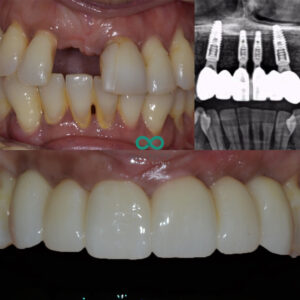

After a careful assessment we provided this patient with a solution to replace her teeth and not have to wear a removable denture again. Our solution was to replace the 6 teeth with 4 Straumann Dental Implants along with a bone graft and a gum graft. The bone and gum graft were very important to this treatment as it enables our team to restore the health of the supporting tissues as well as to recreate natural gum contours so that we do not need to rely on ‘pink porcelain’ to mimic ‘natural tooth shapes’.

We meticulously provided this treatment plan over a period of 6 months to ensure the foundations were built to last – long term results are achieved by undergoing a careful and patient approach to treatment and this is most important when providing dental implant treatment with bone and gum grafting. A temporary smile was provided to the patient during this whole time to ensure she could continue to live her life with minimal stress with regards to her smile.

The end result was one of a natural smile. A smile that she could feel comfortable with. We designed this smile by referring to the exisitng tooth shapes to ensure that we conformed to providing her with the best version of what could have easily been her own teeth. This is he ultimate test for restoring a smile – does it look like a smile that the patient naturally had or does it look like a dentist has created that smile?